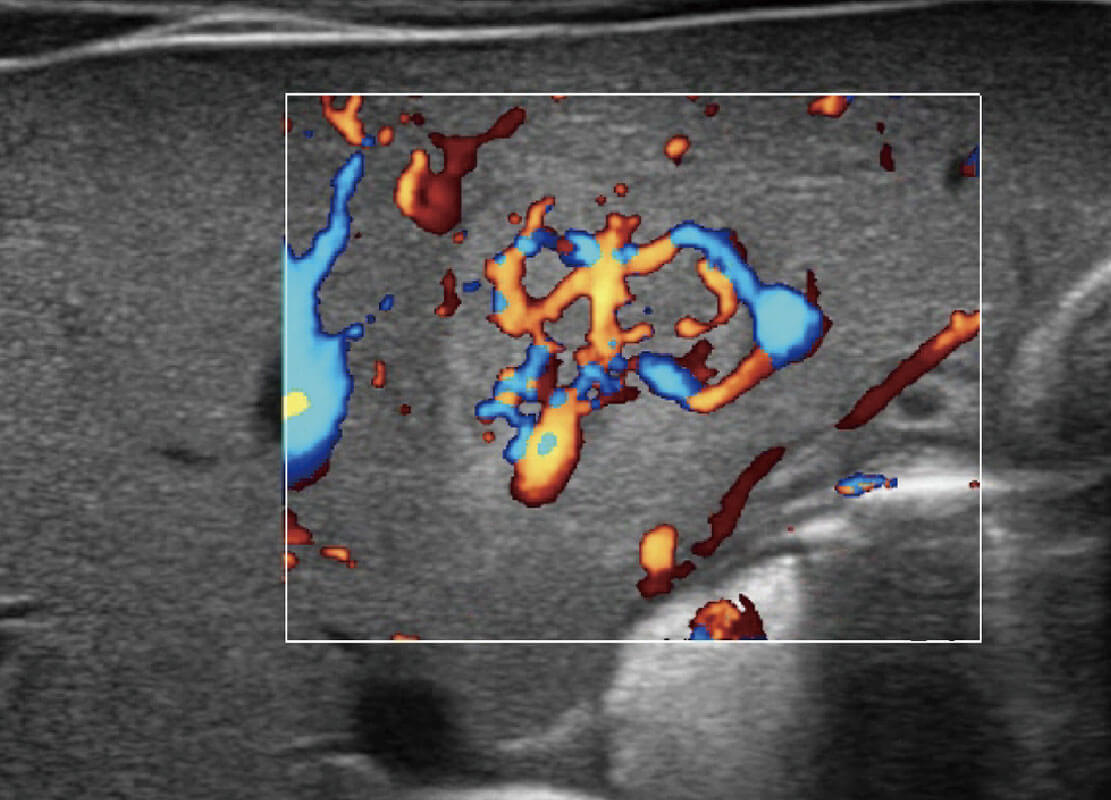

乳腺超声 / 新生儿

P60搭载宽频带线阵探头、宽景成像、弹性成像技术,为您提供乳腺应用方案。P60支持高频相控阵探头、线阵探头、腹部高频探头、腹部微凸探头等,丰富的探头群搭载敏感的彩色血流成像,适用于新生儿多种脏器检测要求,满足新生儿筛查需求。

• 乳腺导管癌

• 乳腺癌显微血流

• 新生儿肝血管癌

• 新生儿脊髓圆锥

• 新生儿心脏